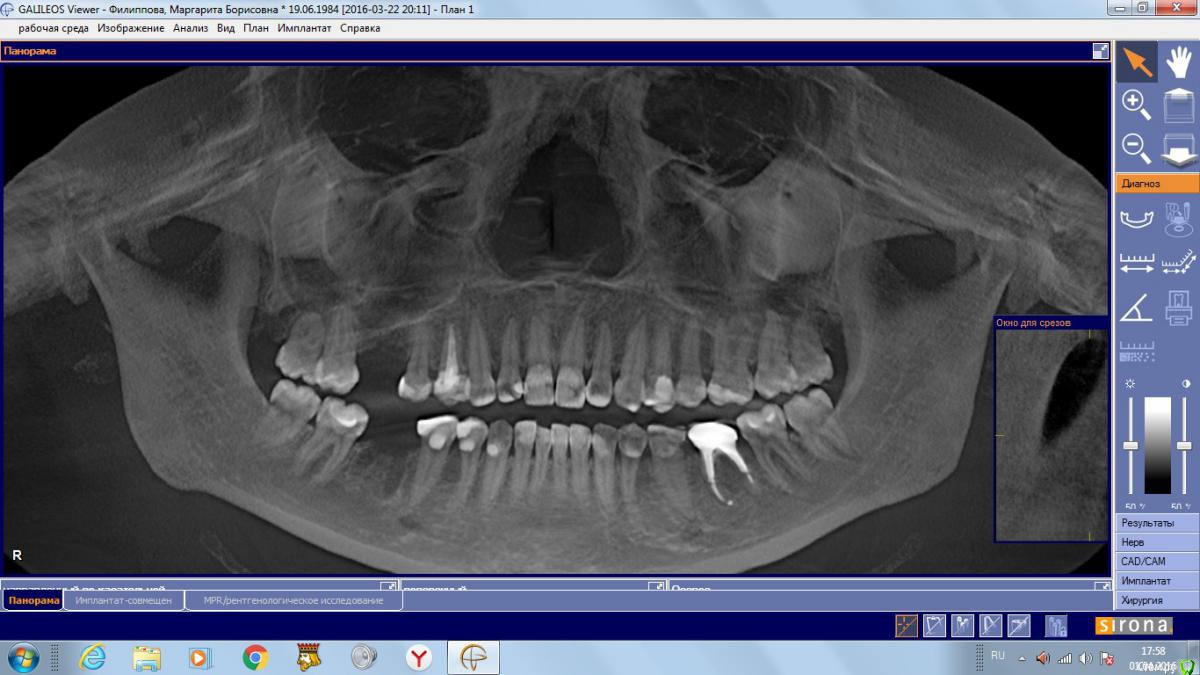

Маргарита19 Опубликовано 2 апреля, 2016 Автор Поделиться Опубликовано 2 апреля, 2016 Спасибо за ответ. Вот такой скрин подойдёт? Ссылка на комментарий

red_butler Опубликовано 2 апреля, 2016 Поделиться Опубликовано 2 апреля, 2016 Спасибо за ответ. Вот такой скрин подойдёт?Не совсем, но похоже можно закрытым синуслифтом обойтись. Скрин области интереса нужен в щечно - небной плоскость, а Вы выкладываете реконструкцию панорамы. 1 Ссылка на комментарий